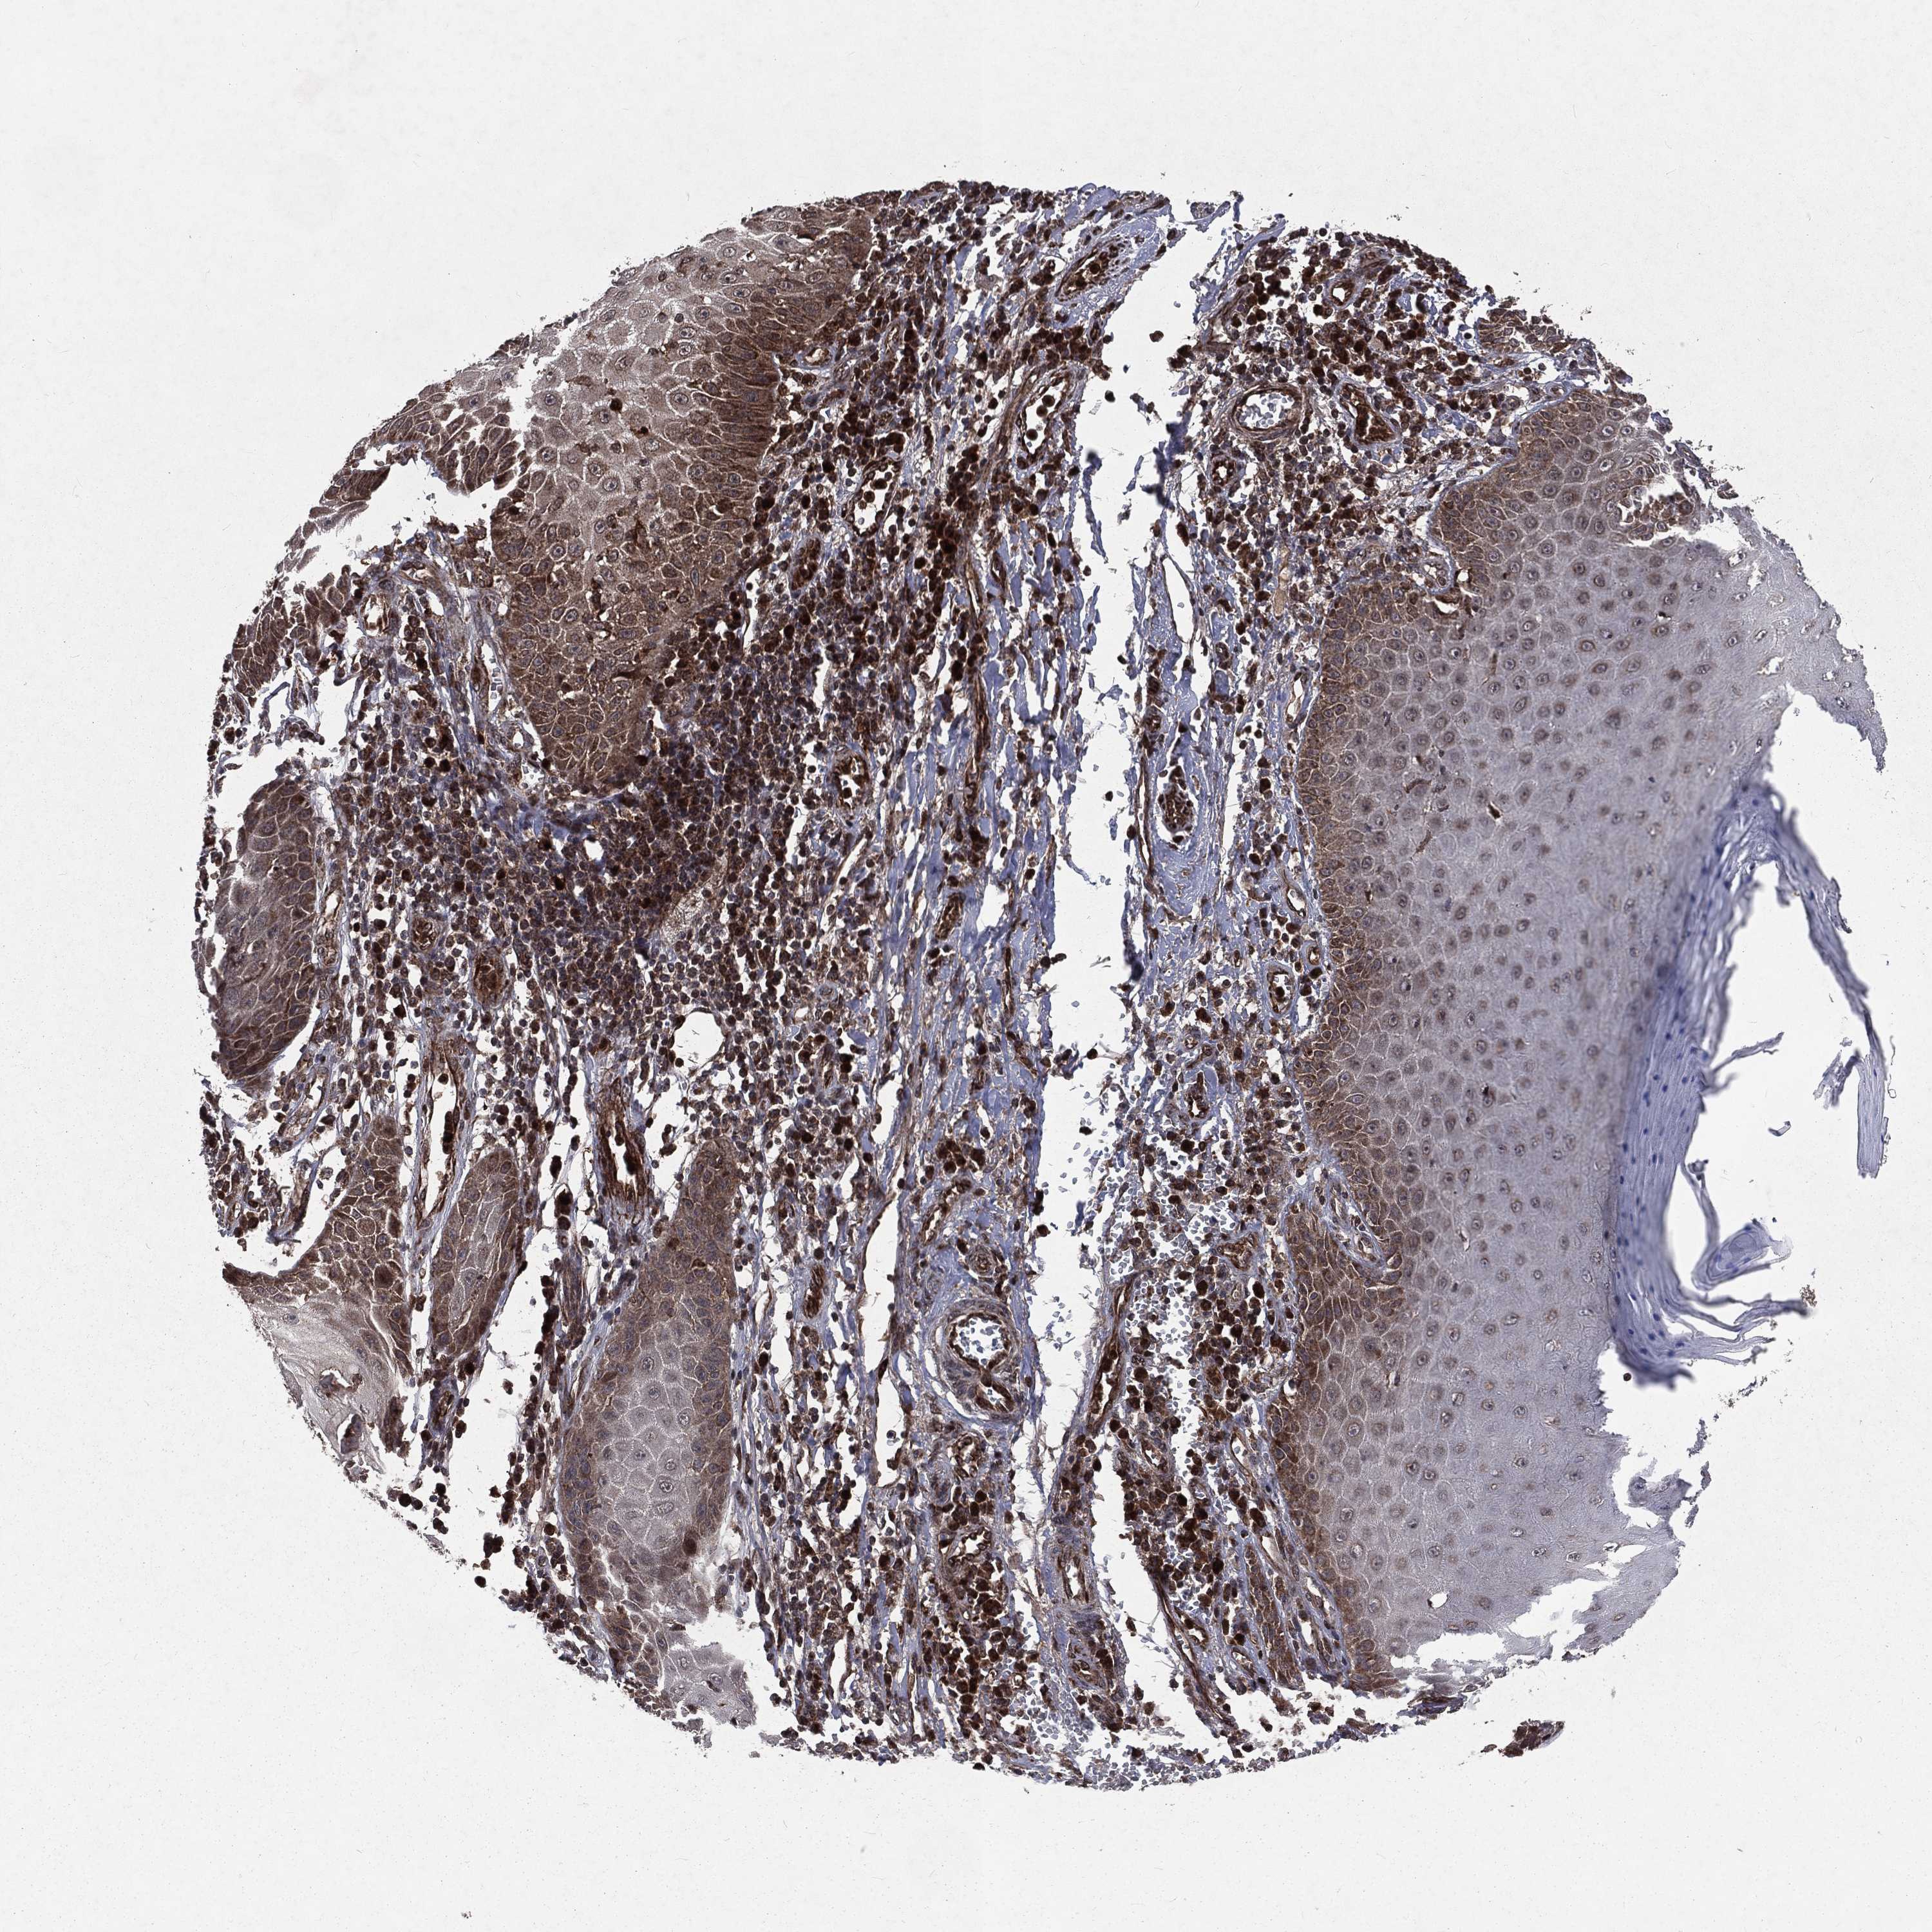

SKIN CANCER - Protein expressioni

A mouse-over function shows sample information and annotation data. Click on an image to view it in a full screen mode. Samples can be filtered based on level of antibody staining by selecting one or several of the following categories: high, medium, low and not detected. The assay and annotation is described here.

Antibody stainingi

Antibody staining in the annotated cell types in the current human tissue is reported as not detected, low, medium, or high, based on conventional immunohistochemistry profiling in selected tissues. This score is based on the combination of the staining intensity and fraction of stained cells.

Each image is clickable and will lead to virtual microscopy that enables deeper exploration of all samples and also displays staining intensity scores, fraction scores and subcellular localization as well as patient and tissue information for each sample.

Antibody HPA061571

Staining

High

Medium

Low

Not detected

Intensity

Strong

Moderate

Weak

Negative

Quantity

>75%

75%-25%

<25%

None

Location

Nuclear

Cytoplasmic/membranous

Cytoplasmic/membranous,nuclear

Squamous cell carcinoma, NOS

Basal cell carcinoma